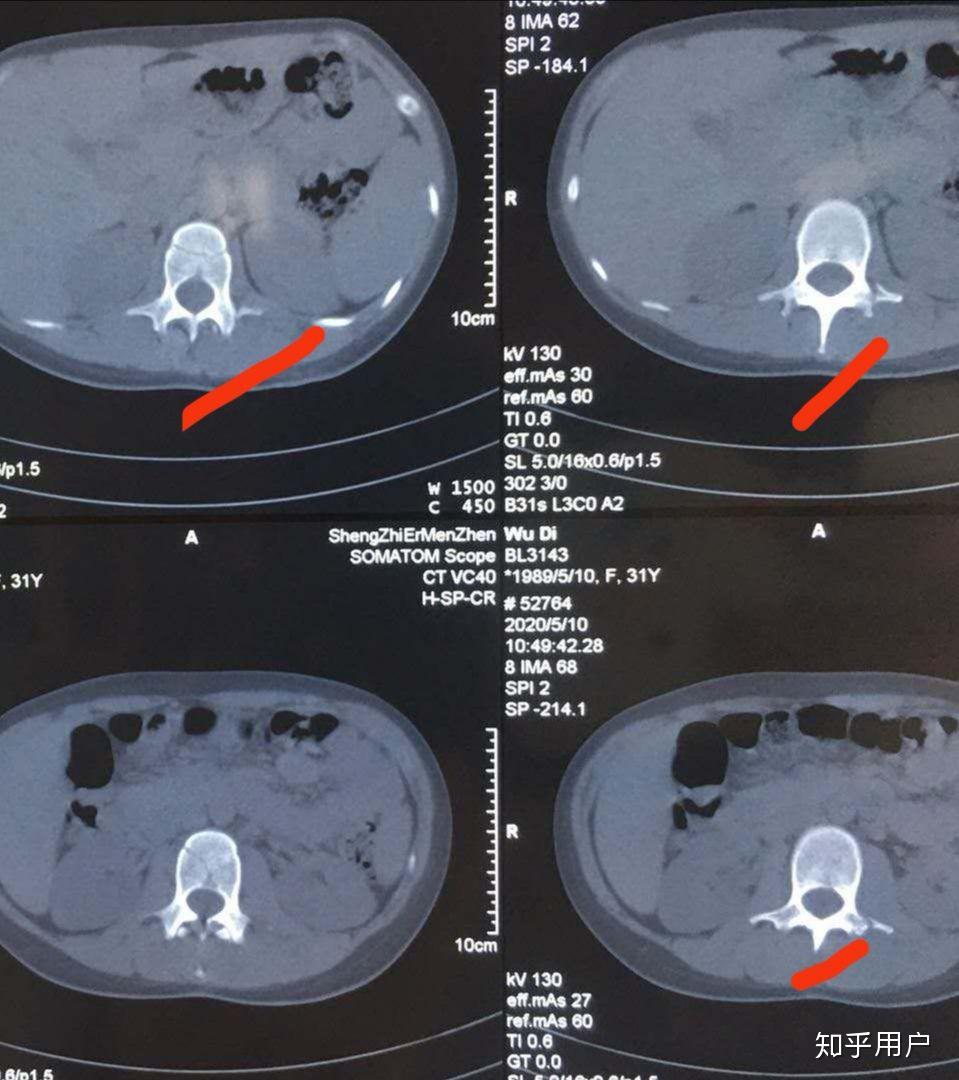

腰椎骨折右侧横突骨折,我想知道这对以后有没有影响,谢谢!